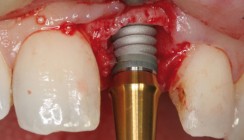

Es wurde eine präoperative Antibiotikaprophylaxe (1 g Amoxicyllin 1-1-1) sowie eine intraorale präoperative Desinfektion mit CHX-Lsg (0,2 %) durchgeführt. Der chirurgische Eingriff erfolgte in Lokalanästhesie (Infiltrationsanästhesie palatinal und vestibulär). Nach beidseitiger krestaler Schnittführung und Darstellung des Alveolarfortsatzes ließen sich die Bohrschablonen eindeutig ohne Fixationsschrauben positionieren. Dies ist allerdings nur im gut konturierten Knochenlager möglich, andernfalls kann die Schablone auch mit Fixationsschrauben befestigt werden. Die Bohrhülsen können offen oder geschlossen gewählt werden. In diesem Fall wurde eine geschlossene Führung gewählt. Das geschlossene System ermöglicht dem Behandler eine sichere Führung der Spiralbohrer. Die Bohrhülsen geben die Richtung für die Spiralbohrer exakt vor („sleeve on drill“) und dienen gleichzeitig als Tiefenstopp, welcher dafür sorgt, dass die virtuell geplante Bohrtiefe nicht überschritten werden kann. Die Aufbereitung des Implantatbettes erfolgt nach Operationsprotokoll des Implantatsystems. Danach wurden die Implantate unter Führung der Operationsschablone eingebracht und nacheinander mittels Fixierungsabutments versehen. Die Fixierungsabutments dienen der zusätzlichen Befestigung und Sicherung der Bohrschablone an ihrer vorab geplanten Position (Abb. 6). Eine reine externe Kühlung, wie bei vielen konventionellen Implantatsystemen üblich, ist bei hartem Knochen und navigiertem Vorgehen nicht ausreichend. Die Kühlflüssigkeit erreicht bei extralangen Bohrern und Verwendung einer Schablone die Bohrerspitze im Knochen nur unzureichend. Dies kann zu Überhitzungsnekrosen führen. Fast alle Bohrschablonensysteme haben hierfür vorgefertigte Löcher, durch welche manuell eine Kühlung, durch die Assistenz mit Kochsalzlösung vorgenommen werden sollte. Die Möglichkeit einer zusätzlichen Innenkühlung ist nur bei bestimmten Systemen möglich und nicht unumstritten (Hygiene/Verbolzung durch Knochenspäne). In dem oben beschriebenen Fall ließen sich die Implantate komplikationslos setzen, und auch beim Einbringen zeigten alle Implantate Insertionsdrehmomente zwischen 35 und 50 Ncm, womit eine Sofortversorgung möglich war (Abb. 7 und 8).